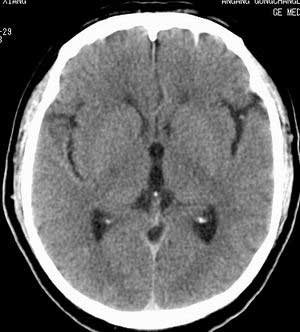

患者男,58岁。耳爆震伤后耳聋2年余,而后双耳道肿胀,间断性流脓。近一月来头痛、恶心、呕吐,右眼红痛,不能入眠。

在平扫时,见右侧枕骨下方小脑半球表面带状模糊稍高密度影,考虑为耳源性脑内感染。

平扫右侧岩骨与枕骨交角内侧脑质内见淡片状密度增高影,内缘清晰。增强图象上未见明显显示。

考虑:1)伪影可能,建议复查头ct平扫。

2)加照头ct骨窗,以显示乳突气房内是否有病变。

右枕颅骨内板下高密度应该是窦的变异,和其症状应该无关,根据病史另找原因吧。[em16]

条状高密度为小脑幕吧

条状高密度为小脑幕

横窦乙状窦。